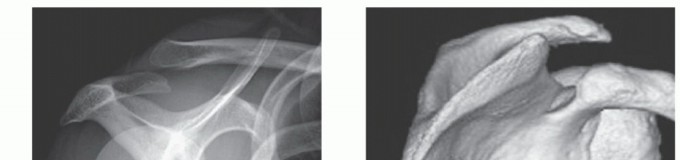

While standard anteroposterior and scapular Y radiographs can rule out gross abnormalities, advanced cross-sectional imaging is mandatory for surgical planning.

Computed Tomography (CT) with 3D volumetric reconstruction is the gold standard for evaluating the osseous morphology of the superomedial angle. It precisely delineates the anterior curvature of the scapula, identifies osteochondromas, and assesses thoracic cage congruency.